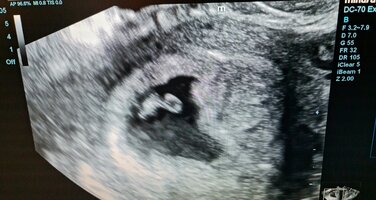

Mulla kävi ultrassa aika samallalailla, olisi pitänyt olla 7+1, mittojen mukaan 6+0, sydän sykki. Kätilön mukaan kaikki vaikutti olevan ihan hyvin. Mutta kun muistelen taakse päin edellisiä raskauksia, oli tilanne melko sama ja myöhemmin koko kuitenkin vastasi lähemmin alkuperäistä laskettua aikaa. Toki nyt raskauduin heti pillereiden poisjäännin jälkeen, niin kierto voisiko olla pidempi, mutta tuon ultran hedelmöittymisen mukaan en mitenkään olisi voinut saada raskaustestiin plussaa, silloin kun sain, eikä myöskään peitto ole siihen aikaan heilunut. Eilen olin neuvolassa ja neuvola hoitaja oli sitä mieltä, että jatketaan sillä alkuperäisellä lasketulla ajalla ja katsotaan sitä sitten nt-ultran jälkeen.Täällä ollaanKävin tosiaan eilen varhaisultrassa. Periaatteessa kaikki oli hyvin. Kaikki löytyi mitä pitikin, kohtuontelo (tai mikä se oikea termi nyt olikaan) oli siisti ja alkion sydän sykki selvästi. Alkio oli kuitenkin selvästi pienempi kuin luulin. Olin laskenut, että eilen olis ollut jo rv 7+2 tai ehkä 7+0, mutta kätilön saama mitta 6,1 cm vastasikin vain rv 6+3:a

Onpa jännittävää!Mä tuun kertomaan teille tännekin, että meidän game over ei ollutkaan vielä game over. Maanantaina musta tehtiin siis lähete julkiselle ja keskiviikkona pääsin käymään siellä lääkärissä ja meidän Papu oli kasvanut kahdessa päivässä kaksi päivää ja sydän oli alkanut lyödä. Se lääkäri ultrasi tosi pitkään ennen kuin se sanoi mitään ( ja aivan ihana kätilö jutteli mulle kaikkea muuta ja piti kädestä) ja kun kuulin ne sanat että täällä on syke niin vastasin: että eikä oo, sä valehtelet. Mutta niin se pieni sydän pamppaili (ja katottiin se aika monta kertaa mun toiveesta). Meillä on sama tilanne kun @Nooora lla että peittojen heiluttelut ja plussat ei mee millään tavalla yhteen nyt viikkojen kanssa ja tottakai jännittää aivan hirvittävästi mitä tuleman pitää. Kahen viikon päästä ollaan viisaampia että mihin suuntaan on menty. Päivä kerrallaan eteenpäin. Mun kohtu on jossai todella perällä joten molemmat ultraajat on todenneet että näkyvyys on huono. Toki myös se maanantain ultraaja totesi että se ei vaikuttanut siihen hänen näkemykseensä siitä, että kyseessä on keskeytynyt keskenmeno ja hän käytti silloin sanoja ”en halua antaa teille yhtään turhaa toivoa”.